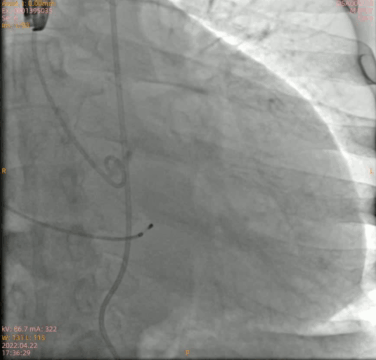

主动脉根部造影